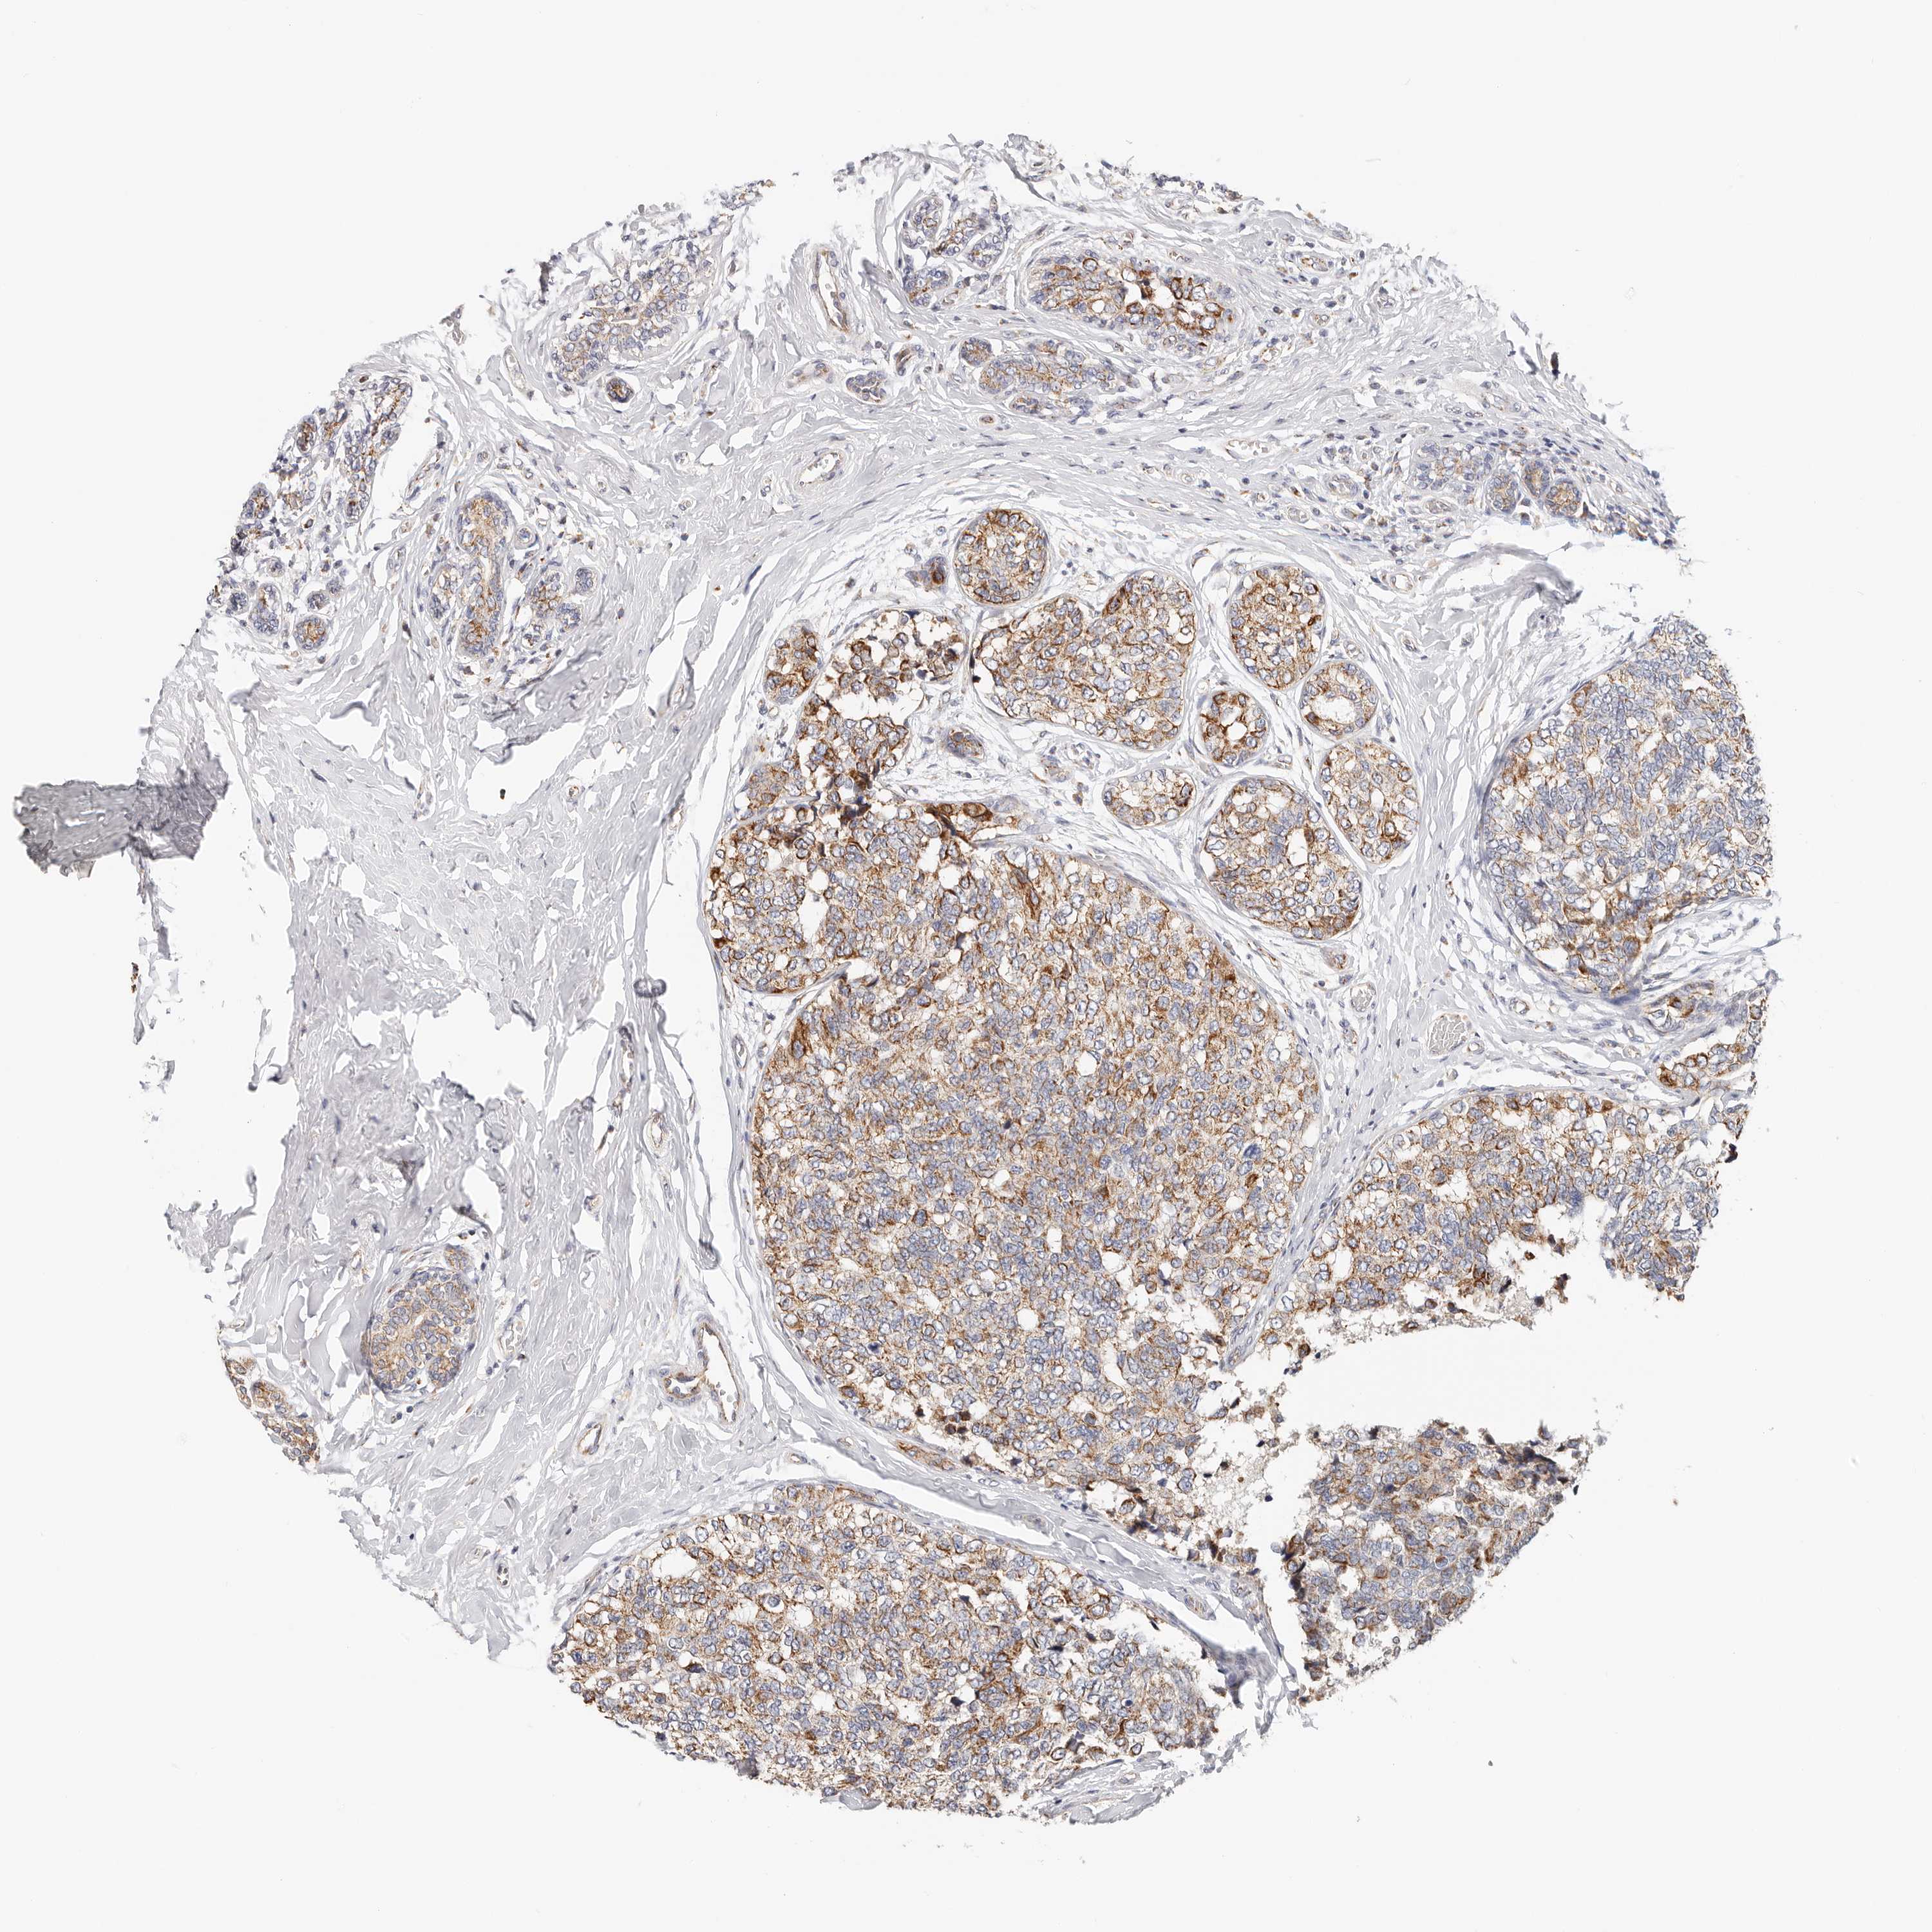

CANCER BREAST CANCER Show tissue menu

BRCA TCGA BRCA VALIDATION PROTEIN EXPRESSION

Breast cancer

Human cancer